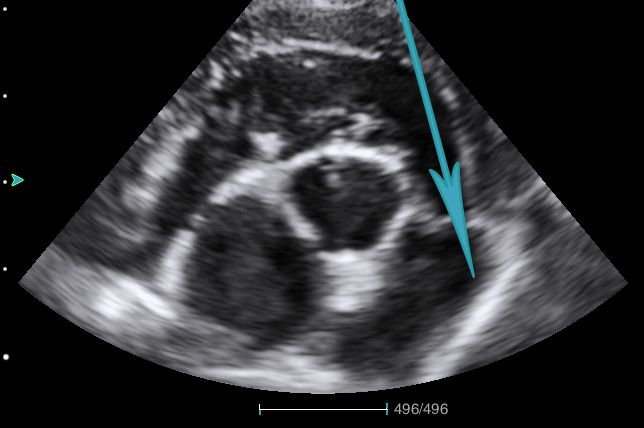

Above: The parasternal short axis view at the level of the aortic valve. Your CW Doppler beam should follow the path of the arrow – through the RVOT and pulmonary valve.

You can rule out pulmonary stenosis or outflow tract obstruction through visual inspection, and by using your Continuous Wave (CW) Doppler. This is most easily performed in the same view you take your LA:Ao ratio from. The leaflets of the pulmonary valve are usually well seen from this view, and should be thin and mobile. This same view is also ideal for aligning your CW Doppler beam through the valve to obtain a peak velocity. You can convert this into a pressure gradient using the simplified Bernoulli equation, 4V². The pressure gradient through the pulmonary valve should be less than 20mmHg in dogs.